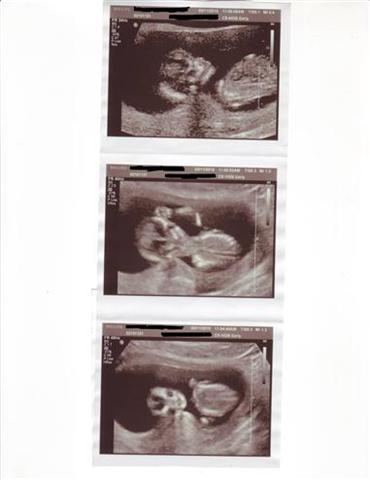

We had our NT Scan yesterday and 12 weeks dr. appt. I am 12w4d and measuring 13 weeks. The ultrasound look beautiful! THe doctor and technician said the baby looks great!

We saw the legs, and arms, and ugh, we are just in love with our little love bug!

Here are some pics from the ultra sound. I can't believe the one with the arm waving! I am so relieved and feel like I can really start to enjoy being pregnant!

and those are awesome sono pics!

Glad you had a great appointment! I love the picture with the baby waving!

I'm glad your scan went well. The sonogram pics came out great! I love the middle one where it looks like your LO is 'fist pumping' LOL